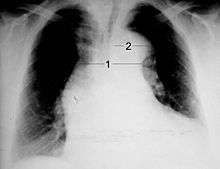

Chest X-ray

Aortic dissection on CXR: Note is made of a wide aortic knob.

Widening of the mediastinum on an X-ray of the chest has moderate sensitivity in the setting of an ascending aortic dissection. However, it has low specificity, as many other conditions can cause a widening of the mediastinum on chest X-ray.

The calcium sign, the separation of the intimal calcification from the outer aortic soft tissue border by 10 mm, is a finding on chest X-ray that suggests aortic dissection.

Pleural effusions may be seen on chest X-ray, more commonly in descending aortic dissections. If seen, they are typically in the left hemithorax.

Other findings include obliteration of the aortic knob, depression of the left mainstem bronchus, loss of the paratracheal stripe, and tracheal deviation.

About 12 to 20% of individuals presenting with an aortic dissection have a "normal" chest X-ray; therefore, a normal chest radiograph does not rule out aortic dissection. If the clinical index of suspicion is high, ruling out dissection with another imaging modality (CT angiogram, MRA, aortogram, or transesophageal echo)is imperative.